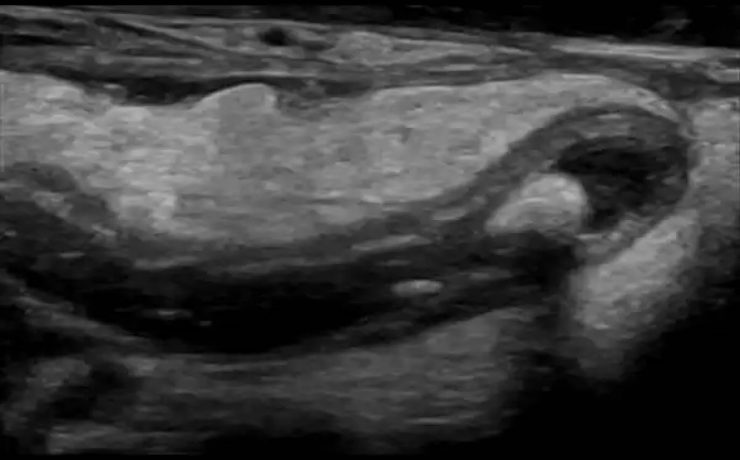

El síndrome de Rokitansky, es la anomalía más grave del tracto reproductivo femenino. Consiste en la ausencia congénita de vagina y útero ausente o rudimentario, como consecuencia de la falla en el desarrollo Mûlleriano de la vagina y el útero. Este síndrome fue descrito por Rokitansky en 1838. Es la